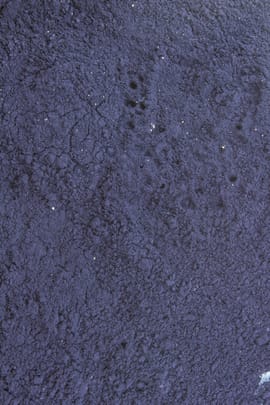

Geschmack:

bitter, salzig

Geschmack:

bitter, salzig